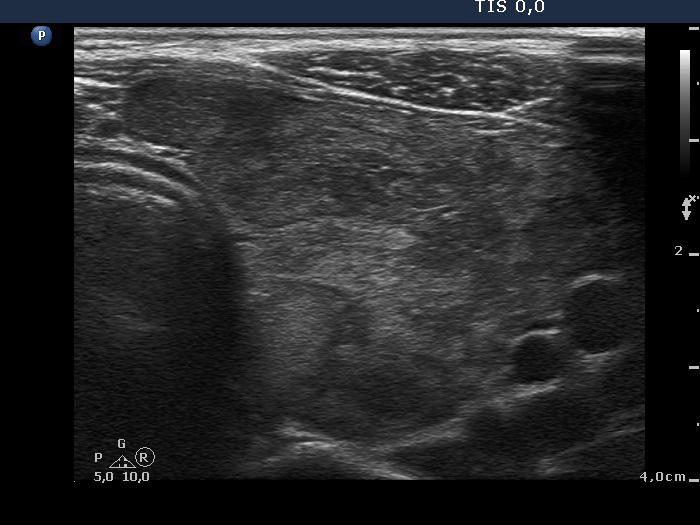

Examination before surgery (first row of images):

Clinical data: A 21-year-old woman requested a second opinion. She has been treated for Graves' hyperthyroidism for three years. The hyperthyroidism relapsed two times. She suffered from mild exophthalmos and occasionally diplopia. Actually, she had no complaints.

Palpation: The thyroid lobes were enlarged. There were no palpable nodules.

Result of blood test: subclinical hyperthyroidism on daily 15 mg methimazole therapy (TSH 0.001 mIU/L, FT4 12.9 pM/L, FT3 4.11 pM/L).

Ultrasonography. The thyroids were echonormal and contained hypoechogenic discrete areas none of them corresponded to a nodule. The echogenicity index was around 30%. The vascularization was average.Surgery was advised. Total thyroidectomy was performed. Histopathology disclosed diffuse goiter, focal lymphocytic thyroiditis.